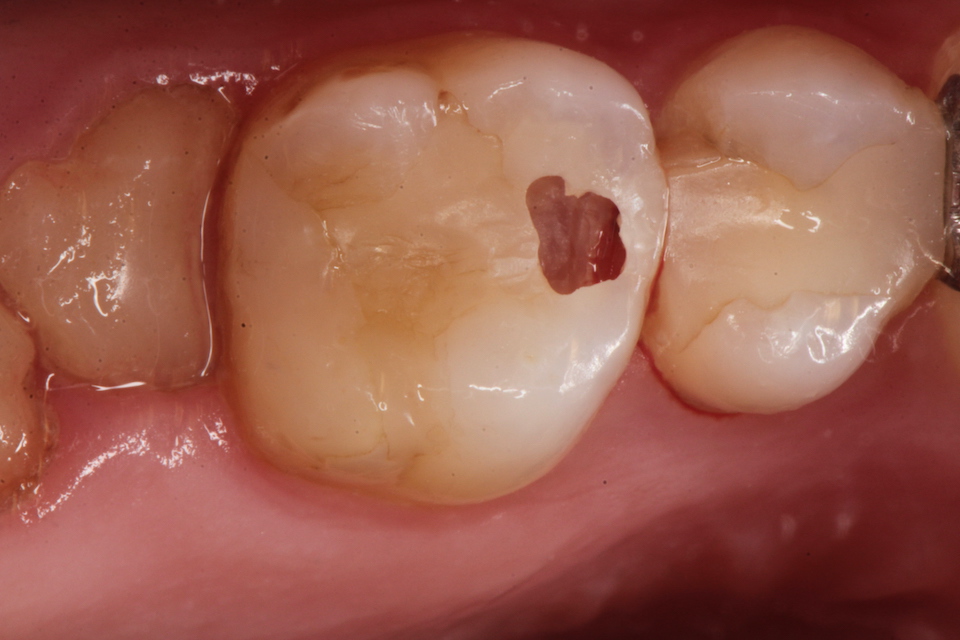

下顎7番の頬側歯茎部カリエスの原因 2025.06.04